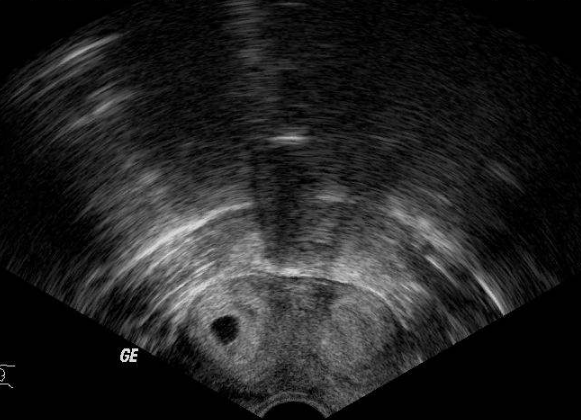

雙角子宮圖片

雙角子宮 (55)